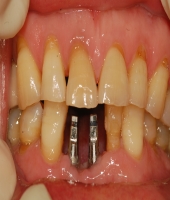

| ● 진료과목 : [임플란트] 치주환자의 보철치료

| ● 내용 : 60대 치주환자의 보철치료 |